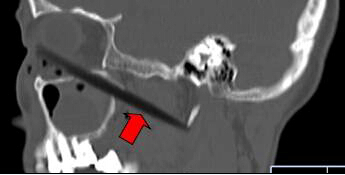

CT顯示筷子還插在腦部

取出的斷筷有9厘米

上周三,62歲的依姆林瓊(化名)在南平家中,有人在揮舞筷子時,將筷子從她右眼眶插入,鼻孔瞬間出血。家人心急,用老虎鉗將筷子外端夾斷,剩下半截筷子嵌在頭面部,之后將其緊急送到福建醫(yī)科大學(xué)附一醫(yī)院。經(jīng)過1個多小時的緊急手術(shù),9厘米長的斷筷被取出,由于筷子未插中眼球,患者眼睛未受影響。附一醫(yī)院耳鼻喉科副主任醫(yī)師張暉萍提醒,千萬不可自行強(qiáng)拔已插入體內(nèi)的物體。傷者被送到附一醫(yī)院時,醫(yī)生幾乎都看不到筷子了。在醫(yī)生的詢問下,家屬這才說,當(dāng)時,他們一心急,用老虎鉗將筷子外端夾斷。這下棘手了。若筷子是完整的還容易拔出,這下完全埋在眼眶下,可怎么取出?影像學(xué)檢查顯示,筷子就靠近視神經(jīng)管、頜內(nèi)血管分支,末端位于頸部大動脈的前方。手術(shù)稍有不慎,就可能大出血。為了取出斷筷,附一醫(yī)院耳鼻喉科、頜面外科、眼科、影像科馬上聯(lián)合會診,擬定了三套手術(shù)方案。第一方案,從插入口直接拔;第二方案,從鼻腔取;第三方案,鋸開眼眶取斷筷。最終,大家選擇了第一方案,因為創(chuàng)傷最小,由耳鼻咽喉科張暉萍副主任醫(yī)師和眼科朱學(xué)軍主任醫(yī)師聯(lián)合急診手術(shù)。醫(yī)生們先從眼眶內(nèi)切開傷口1厘米,才看到筷子斷端,順著原先插入口,在鼻窺鏡的幫助下,邊夾邊推,將筷子順利取出。取出的竹筷長達(dá)9cm,周圍有大量膿液。經(jīng)過多日抗感染治療,前日,老人才出院。